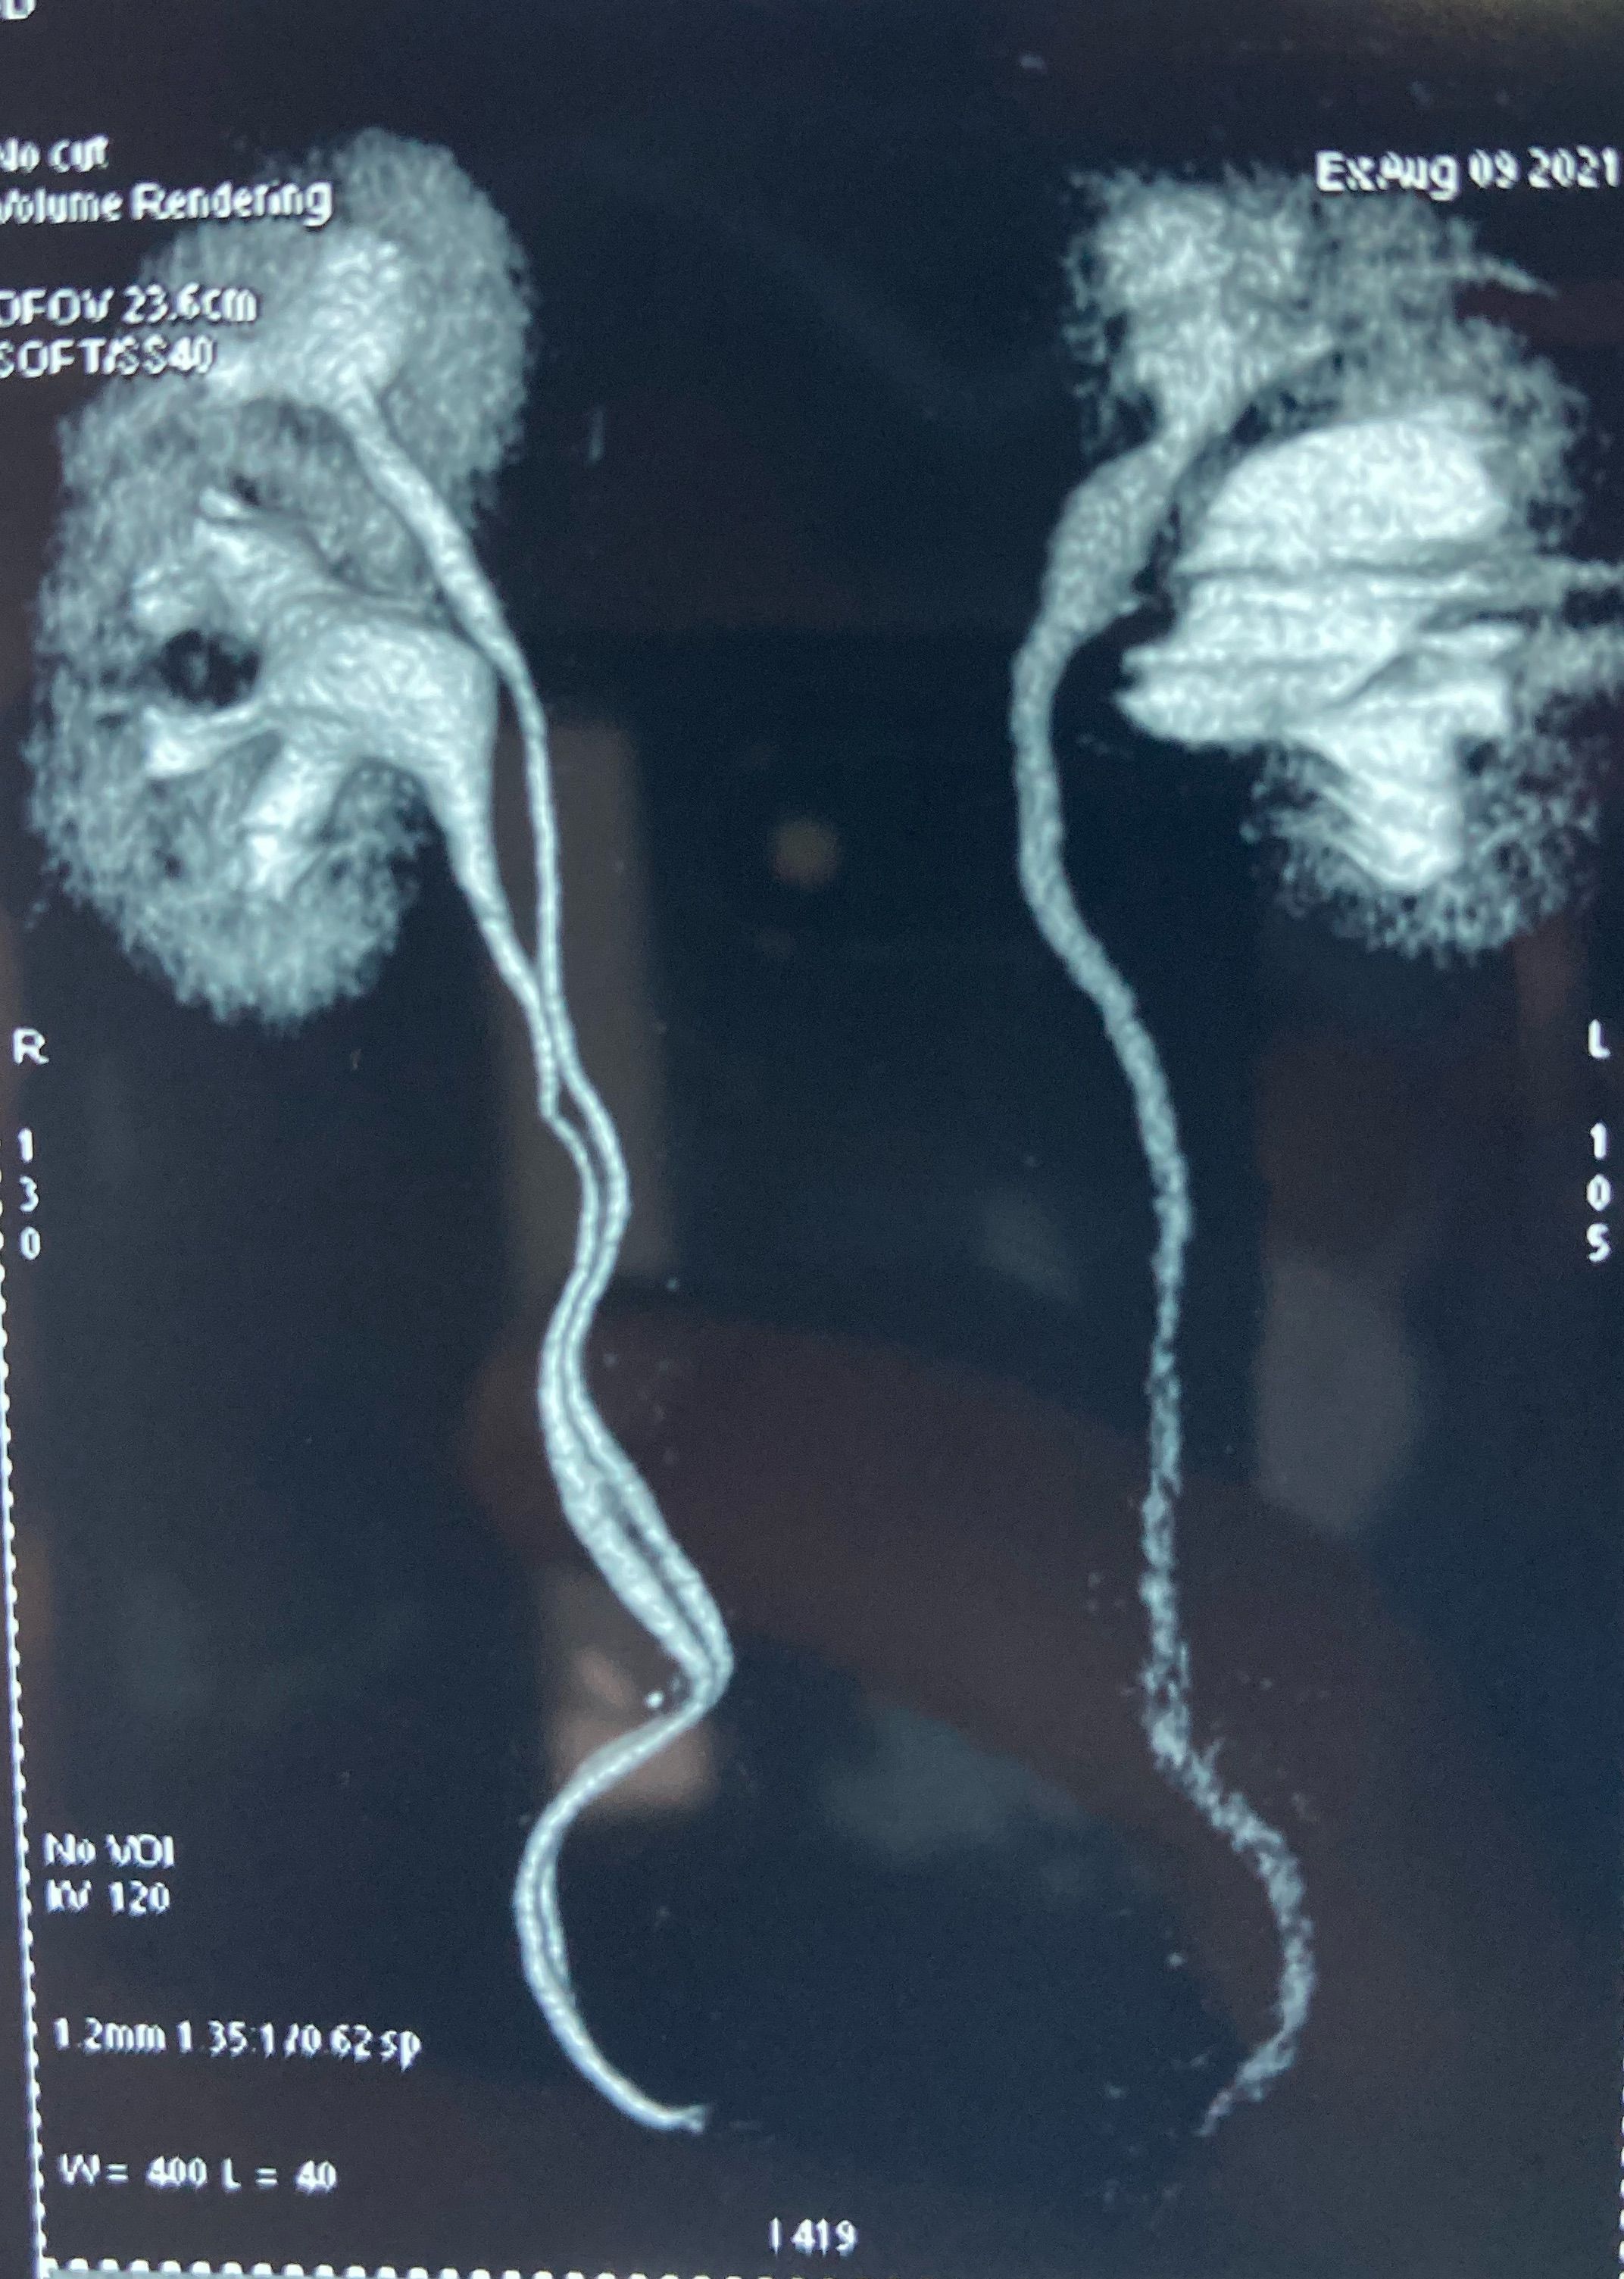

With duplex kidney and complete ureteral duplication, the upper renal and lower renal moieties are drained by separate ureters, each having its own ureteral orifice in the bladder. upper renal moiety ureter has ectopic insertion medial and inferior to the lower renal moiety ureter, and frequently ends in a ureterocele lower renal moiety ureter has orthotopic insertion lateral and superior to the upper renal moiety ureter, and vesicoureteral reflux can occur